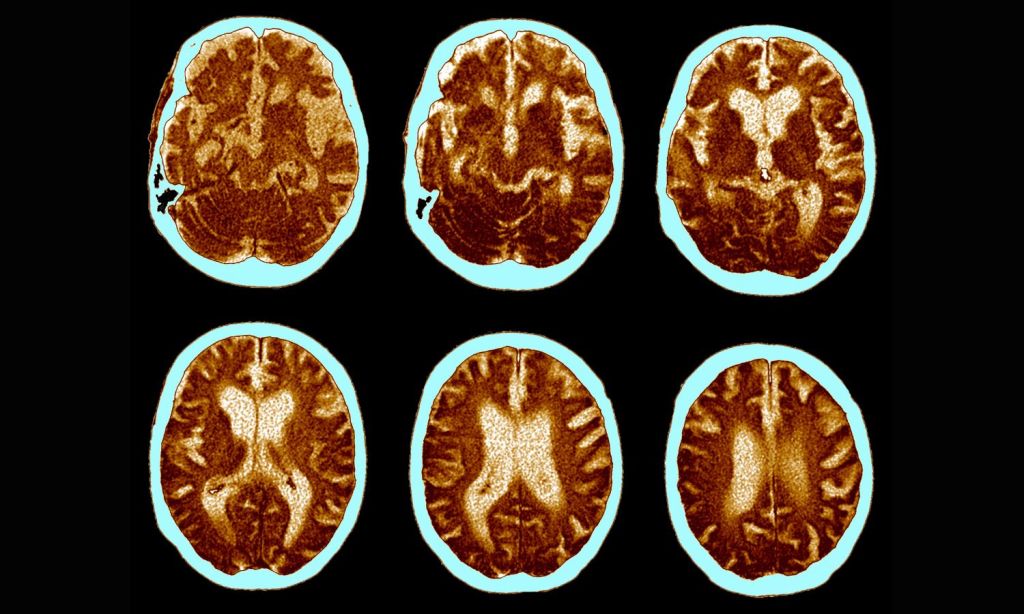

It’s believed to occur when levels of an amino acid called amyloid beta build up in the brain, collecting as amyloid plaque and tau proteins. The ability of our brains to clear these proteins becomes more limited over time, but people with Alzheimer’s see a greater-than-normal buildup. The amyloid beta build-up effectively kills brain cells and limits the connections between them, shrinking the brain and resulting in cognitive decline.